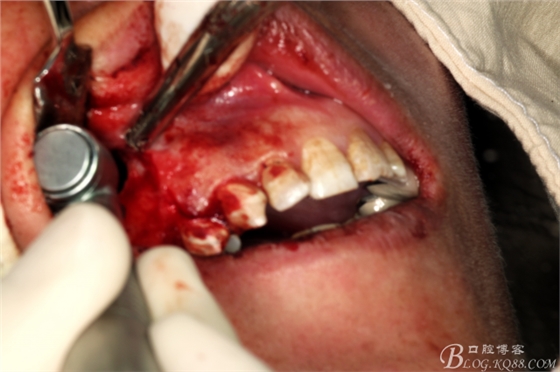

圖11.囊壁摘除后,暴露的16腭側(cè)根尖有少許牙膠尖超填

圖12.高速牙鉆截取16腭根3mm.

圖13.刮除腭側(cè)牙根周?chē)∽兘M織

圖14.切去16近中頰根根尖3mm,并行MTA倒充填